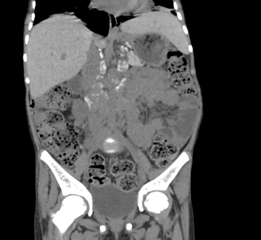

Key Findings: Contrast-enhanced CT of the abdomen and pelvis in this patient

revealed multiple enlarged lymph nodes with characteristic hyperdense coarse

peripheral calcifications distributed throughout the portal, left

gastro-hepatic, pre and para-aortic, aorto-caval and peripancreatic stations,

with the largest measuring 40.8 x 28.9 mm in the aorto-caval region, all

demonstrating uniform post-contrast enhancement (Figure 1).

Figure 1: Coronal reformatted non contrast CT images after the administration

of neutral oral contrast showing multiple retroperitoneal lymph nodes

demonstrating characteristic hyperdense coarse peripheral calcification (as

noted by the arrows) in the left gastro-hepatic, pre- and para-aortic and

aorto-caval groups